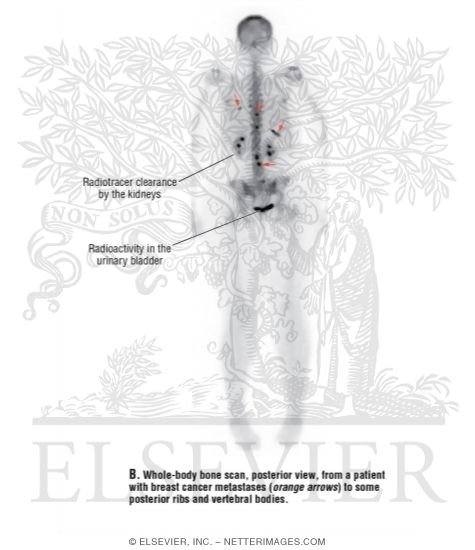

Whole-body Bone Scan, Posterior View, From a Patient With Breast Cancer Metastases to Some Posterior Ribs and Vertebral Bodies

Whole-body Bone Scan, Posterior View, From a Patient With Breast Cancer Metastases to Some Posterior Ribs and Vertebral Bodies